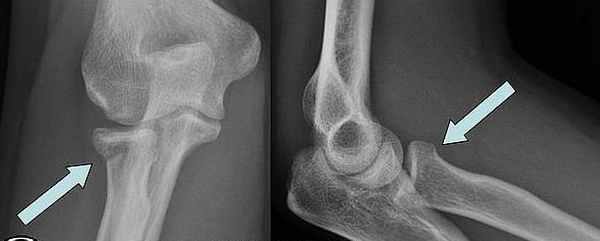

При переломе венечного отростка остеосинтез выполняют 3,5 мм винтом. Для остеосинтеза перелома головки лучевой кости применяют фиксацию малым спонгиозным винтом.

Остеосинтез головки лучевой кости и венечного отростка локтевой винтами.